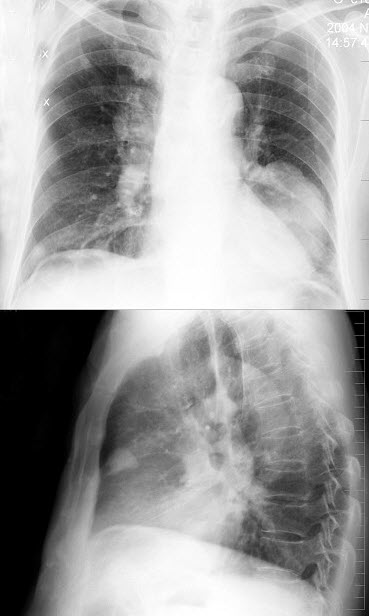

116、单项选择题

男,75岁,胸痛,咳嗽半年,气逼,多年前曾因黑色素瘤手术,胸片如图,最可能的诊断是()

A.原发性肺癌

B.肺结核瘤

C.黑色素瘤肺转移

D.炎性假瘤

E.韦格肉芽肿